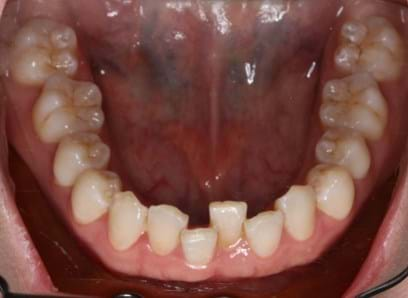

Have you undergone orthodontic treatment during your childhood or teenage years, only to notice your teeth gradually returning to their previous positions? This is more common than you think. Orthodontic relapse refers to the teeth reverting to their original positions after orthodontic treatment, whether with braces or clear aligners. There are a few factors that might contribute to this relapse.